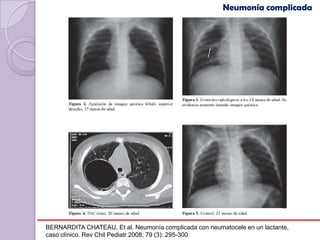

Neumonía complicada

NEUMATOCELE

Es una formación adquirida de contenido aéreo de paredes

delgadas formadas por el parénquima pulmonar adyacente.

Se desarrolla como resultado de necrosis alveolar y

bronquiolar localizada

Se estima una incidencia general de 2-3% de todas las

neumonías

Postinfeccioso generalmente aparece dentro                         de    las

primeras dos semanas de evolución de la neumonía

BERNARDITA CHATEAU, Et al. Neumonía complicada con neumatocele en un lactante,

caso clínico. Rev Chil Pediatr 2008; 79 (3): 295-300